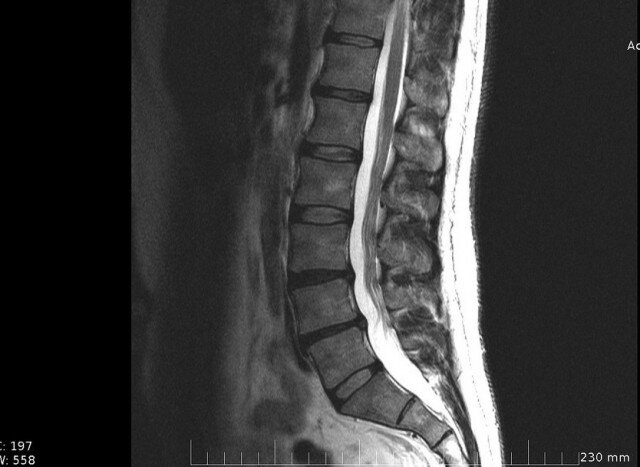

Пояснично-крестцовый отдел позвоночника на МРТ снимке

На серии МРТ поясничного отдела позвоночника физиологический лордоз выпрямлен. Ретролистез L5 позвонка на ~ 4мм. Определяется снижение интенсивности сигнала на Т2-ВИ дисков (в сегментах Th12-L5 минимально, в сегменте L5-S1 выражено), снижение высоты дисков Th12-S1, умеренный артроз межпозвонковых суставов, гипертрофия желтых связок, формирование переднебоковых краевых костных разрастаний L5, S1 позвонков.

Отмечается уплотнение замыкательных пластинок тел позвонков с участками невыраженного субхондрального склероза. Линейные участки отека костного мозга в телах L5, S1 позвонков. Задняя продольная связка уплотнена. Дорсальная медианная грыжа диска L5/S1 до 4,5мм, мигрирующая каудально, деформирующая дуральный мешок, соприкасающаяся с корешками, умеренно суживающая оба межпозвонковых отверстия. Сагиттальный размер позвоночного канала 13мм. Структура содержимого дурального мешка не изменена. Дистальные отделы спинного мозга и конский хвост не смещены, не деформированы, участки патологически изменённого сигнала в веществе мозга не определяются. Ликвородинамика не нарушена. Паравертебральные мягкие ткани не изменены.

Костных деструктивных изменений крестца и копчика не определяется. Определяется отек костного мозга S5 позвонка, с наличием локального участка гипоинтенсивного сигнала на Т1-BИ в дистальных отделах позвонка (нельзя достоверно исключить перелом). Участки жировой дегенерации костного мозга в телах Со1-Со4 позвонков. Признаков отклонений кнутри (вывихов, подвывихов) копчиковых позвонков не определяется, отмечается отклонение копчиковых позвонков от центральной линии вправо.

Заключение: МР-признаки дегенеративно-дистрофических изменений поясничного отдела позвоночника. Грыжа диска L5/S1. Сужение позвоночного канала вторичного генеза. МР-картина не позволяет достоверно исключить перелом S5 позвонка.